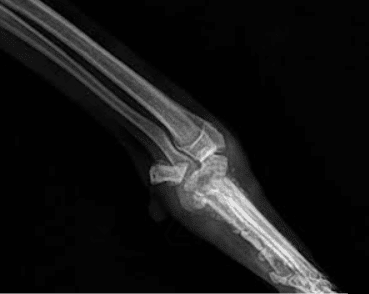

Die liebe Windhund-Mix-Hündin GRACY kam mit einer schweren Beinverletzung und komplett abgemagert ins Shelter. Zur medizinischen Abklärung wurde sie in die Klinik gebracht. Leider sieht es so aus, als könne das Bein nicht gerettet werden, sodass eine Amputation in Betracht gezogen wird. Trotz allem zeigt sie sich unglaublich sanft, kooperativ und geduldig, sie meistert alle Untersuchungen ganz tapfer.